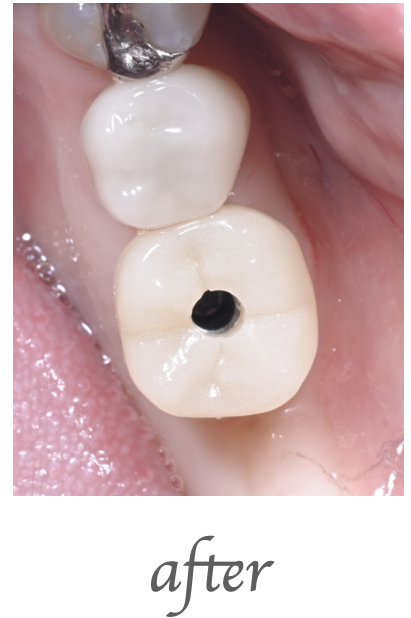

治療内容

右下奥歯の被せの脱離でこられた患者様です。右下の歯の精密根管治療を行いました。

治療期間・回数

治療期間:約2週間 治療回数:3回

費用

¥130,000(税込143,000)

リスク・副作用

処置直後2〜3日は軽微な痛みが出ることがあります。再感染・症状の改善を認めない場合があります。